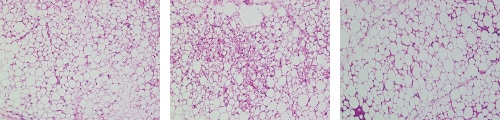

脂肪細胞は、細胞質に脂肪滴と呼ばれる脂肪のかたまりをもっている細胞で、単胞性脂肪細胞(白色脂肪細胞)と多胞性脂肪細胞(褐色脂肪細胞)に分かれます。白色脂肪細胞には大きな脂肪滴がひとつあり、脂肪をたくわえる役割をしています。褐色脂肪細胞には中小の脂肪滴が多数あり、脂肪を燃焼して熱を産生します。

肥満に伴って大型化した白色脂肪細胞が増加すると脂肪細胞の機能不全に陥り、生活習慣病の発症につながります。